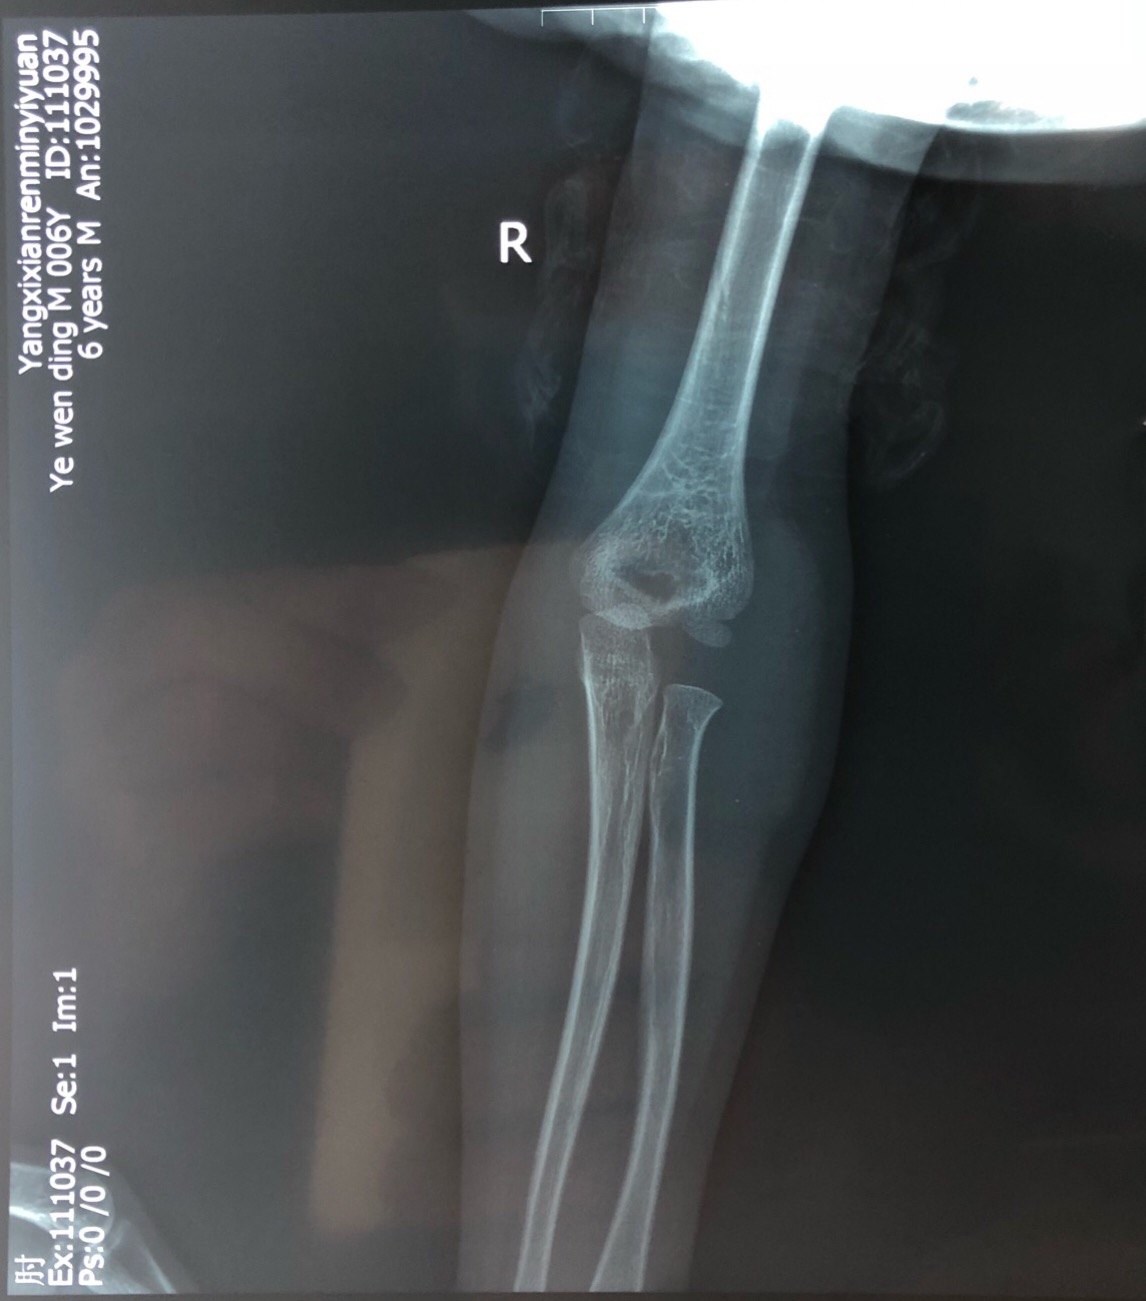

肱骨外髁骨折程度[s0]肱骨外髁骨折分型[s1]肱骨外髁骨折的临床表现[s2]肱骨外髁骨折Ⅲ型复位手法[s3]肱骨外髁骨折,保守治疗可以吗[s4]小儿肱骨外髁骨折[s5]儿童肱骨外髁骨折,医生不说你很可能永远都不会知道的[s6]不同类型的肱骨外髁骨折[s7]肱骨外髁骨折概述[s8]六、肱骨外髁骨折 - 图1[s9]六、肱骨外髁骨折 - 图2[s10]图片[s11]肱骨外髁骨折 m.haodf.com[s12]图片[s13]肱骨外髁骨折[s14]img[s15]肱骨外髁骨折.[s16]分期矫正儿童肱骨外髁骨折不愈合伴肘外翻畸形[s17]肱骨外髁骨折[s18]肱骨外髁骨折翻转90°,复位后克氏针或螺钉固定(自ao)[s19]右肱骨外髁骨折切开复位内固定术[s20]img[s21]img[s22]赵景新's media[s23]一例儿童右肱骨外髁骨折病例[s24]肱骨外髁骨折,保守治疗可以吗[s25]小儿肱骨外髁骨折[s26]肱骨外髁骨折固定[s27]肱骨外髁骨折 www.iiyi.com[s28]小儿肱骨外髁骨折的诊断和治疗[s29]右肱骨内外髁骨折[s30]图36-48 肱骨外髁骨折的不同程度移位 a型无移位;b型中度移位;c型完全移位伴旋转[s31]肱骨外髁骨折 www.haodf.com[s32]肱骨外髁骨折 www.haodf.com[s33]问:左肱骨外髁骨折,左肘关节脱位,6.[s34]儿童肱骨外髁骨折 - 小红书[s35]儿童肘关节损伤之--肱骨外髁骨折[s36]▲右侧肱骨外髁骨折闭合复位克氏针固定及石膏固定术后。“幸亏在掉落的[s37]肱骨外髁骨折 www.guahao.com[s38]肱骨头及外髁骨折,求诊治方案,手术还是非手术[s39]